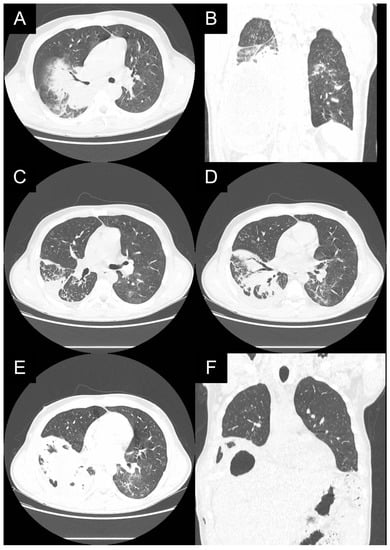

In the presented case, the hepatic lesion ruptured directly to the right lower segmental bronchus S10 as confirmed acutely in a flexible bronchofibersocopy, where large amounts of purulent discharge were lavaged. Chest CT showed communication of the ruptured lesion with the large right airways (Figure 5). This acute respiratory situation required an urgent surgical procedure. The presence of pneumonitis precludes parenchymal resections. A thoracotomy for exploration and meticulous debridement was followed by formation of an open fenestration at the level of the 9th rib to control infection without parenchymal resection (Figure 6). Regular dressing changes and long-term anthelminthics controlled the infection (Figure 7).

Figure 5. (AF): A chest CT of patient 1 showing ruptured continuity of the hepatic lesion. The right lower lobe bronchi are filled with fluid from hepatic lesion. At bronchoscopy, an S10 fistula was detected.